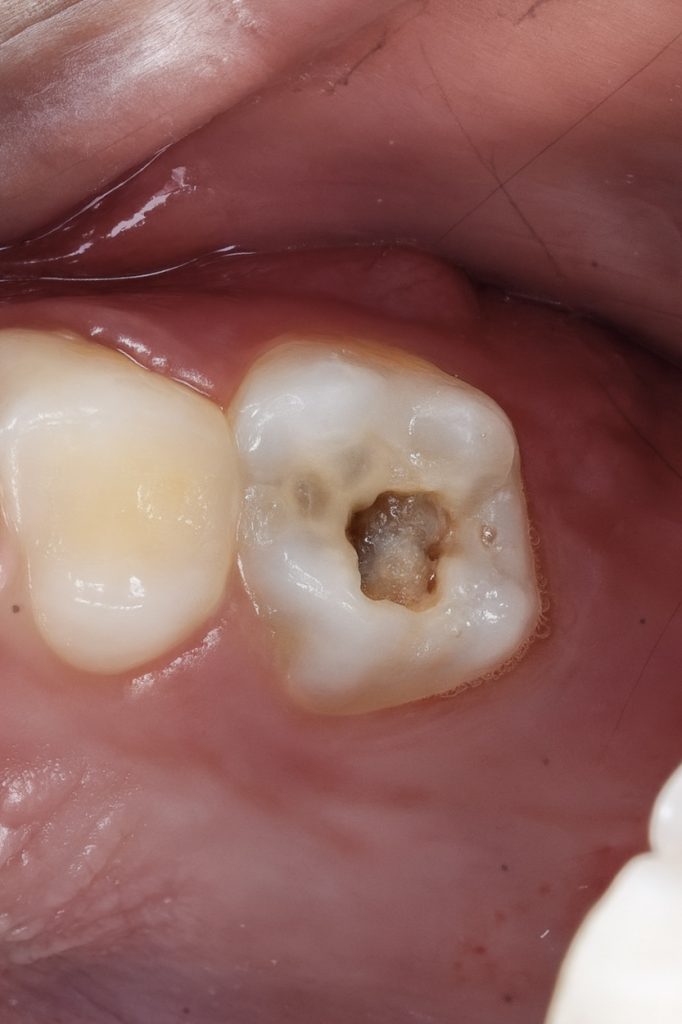

5️⃣ Coronal Seal and Cuspal Coverage Build-Up

A base layer of GC EverX Flow was placed to reinforce weakened dentin. Over it, Tokuyama Estelite Sigma Quick was applied incrementally to reconstruct missing cusps under microscope control (Fig 4). Each increment cured 40 s per surface, ensuring strong adhesion and anatomic contour.

- Fig 4: Incremental composite cuspal coverage using EverX Flow + Tokuyama.